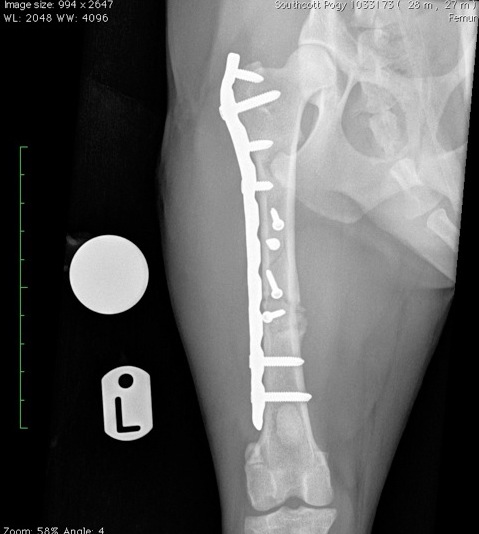

Pogy wurde stationär aufgenommen und stabilisiert. Die Röntgenaufnahmen zeigten komplizierte Frakturen im linken Hinterbein. Das Bein wurde mit Hilfe von Verbänden bis zum nächsten Tag notdürftig stabilisiert, damit Pogy am nächsten Morgen zu einem Spezialisten transportiert werden konnte.

Dort wurde neben weiteren Röntgenaufnahmen auch ein CT angefertigt, um eine ungewöhnliche Splitterfraktur des linken Femur genauer darzustellen. Der CT-Scan zeigte, dass eine der Frakturlinien weit nach proximal fast bis ins Hüftgelenk zog. Konventionelle Schrauben kamen wegen dieser Frakturlinie nicht in Frage. Aufgrund dieser Umstände entschied sich das Expertenteam für den Einsatz einer neuartigen Locking Plate, die den Einsatz von kürzeren Schrauben erlaubte, die keine Auswirkungen auf die Frakturlinie haben sollten. Die schwierige Operation verlief wie geplant.